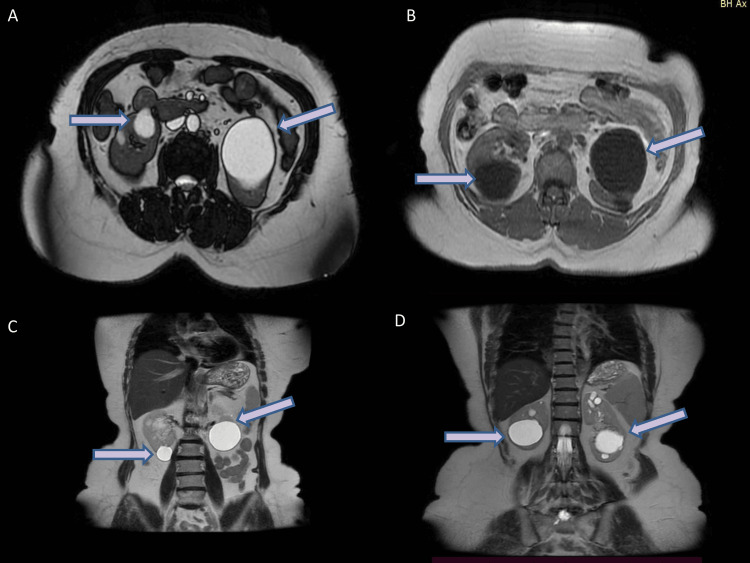

我们报告一例55岁女性慢性无症状血尿,长期诊断为基底膜疾病,表现为高血压恶化和显著程度的蛋白尿进展为慢性肾脏疾病。基因测序鉴定出COL4A4基因(c.1321_1369+3del)的杂合致病性变异,这是一个52个碱基对的缺失,破坏了外显子20/内含子20连接的正常核糖核酸(RNA)剪接。In silico分析预测典型剪接位点的完全缺失,导致iv型胶原的剪接不当和α4链功能障碍。该家族的基因检测证实,在另外两代人中也存在相同的变异。据我们所知,这是第一个报道的家族中c.1321_1369+3del突变是常染色体显性Alport综合征的唯一原因。

We report the case of a 55-year-old woman with chronic asymptomatic hematuria and a longstanding diagnosis of thin basement membrane disease, presenting with worsening hypertension and a significant degree of proteinuria progressing to chronic kidney disease. Genetic sequencing identified a heterozygous pathogenic variant in the COL4A4 gene (c.1321_1369+3del), a 52-base pair deletion that disrupts normal ribonucleic acid (RNA) splicing in the exon 20/intron 20 junction. In silico analysis predicted the complete loss of the canonical splice site, leading to improper splicing and the dysfunction of the α4 chain of type-IV collagen. Genetic testing in the family confirmed the presence of the same variant in two additional generations. To our knowledge, this is the first reported family in which the c.1321_1369+3del mutation is the sole cause of autosomal dominant Alport syndrome.